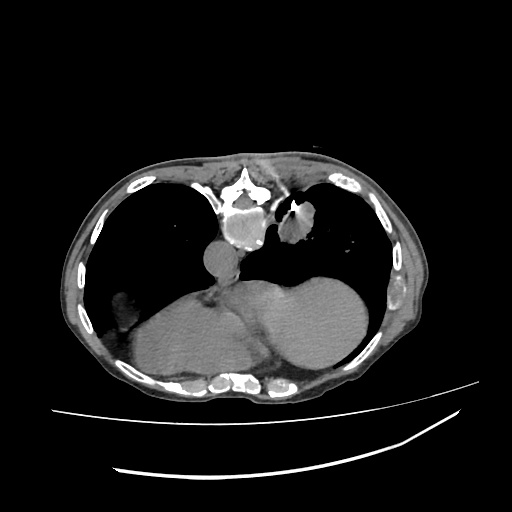

LUNG MASS BIOPSY, 70Y F